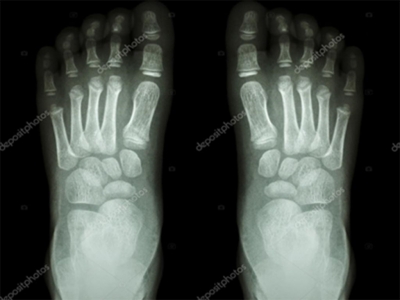

Radiografía del niño de 1 año sin alteraciones

(Fuente: Depositphotos)